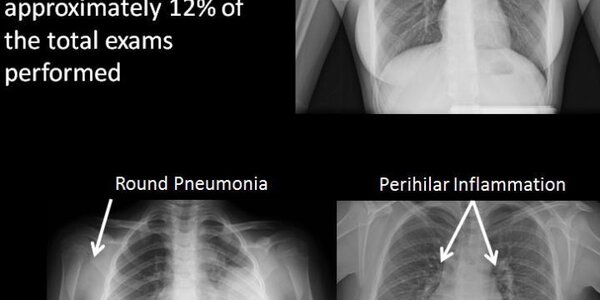

88 Percent Of Chest X-rays Are No Benefit To Children

It's always a good idea to reduce cost and radiation and when it comes to kids and chest X-rays, that cost reduction should be happening a lot more. The authors of a new analysis reviewed data from 719 pediatric chest X-ray exams ordered between 2008 and 2014 in Mayo Clinic's inpatient, outpatient and emergency room settings. The patients undergoing the exams ranged in age from newborn to 17 years old. Of the 719 X-ray exams, 377 exams were ordered for chest pain, 98 indicated syncope (fainting) or presyncope, 21 indicated spells (a general feeling of being unwell or under distress), 37…